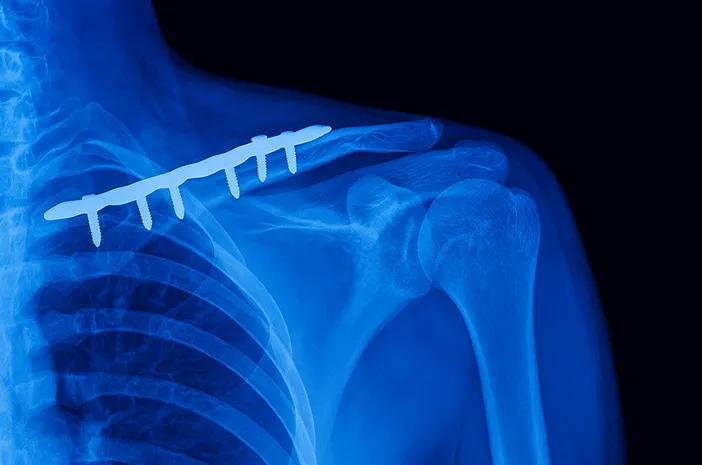

- Plate: Lempengan logam yang dipasang di permukaan tulang dengan sekrup untuk memberikan stabilitas tambahan.

Pen patah tulang, atau dikenal juga sebagai implan ortopedi, adalah perangkat medis yang digunakan untuk menstabilkan dan menyokong tulang yang mengalami fraktur. Pemasangan pen bertujuan untuk menjaga posisi tulang yang benar selama proses penyembuhan.

Prosedur ini umum dilakukan pada kasus patah tulang yang memerlukan fiksasi internal, terutama jika patahan tersebut tidak stabil atau sulit sembuh dengan metode konservatif seperti pemasangan gips.